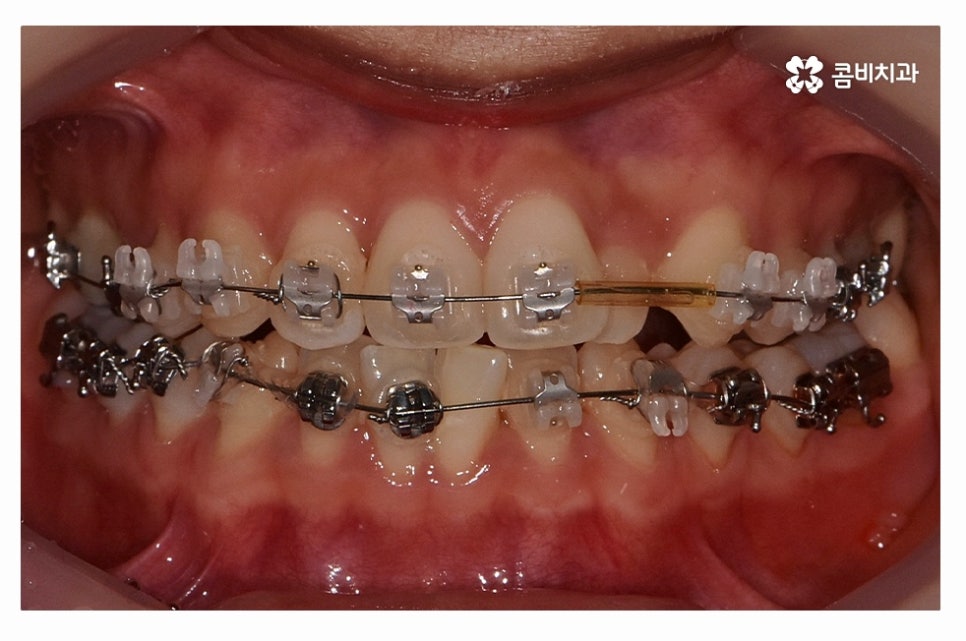

오늘 보여드릴 사례도 덧니교정이 비발치로 진행이 된 사례이며

치아의 이동 공간과 치아 상태, 골격, 얼굴형 등을

종합적으로 판단할 때 비발치로도 진행이 가능했던 사례라고 할 수 있어요.

위 환자분의 사례처럼 클리피씨교정이 보편적으로 많이 활용되고 있는데요.

클리피씨교정은 치아의 이동이 일반 장치에 비해 상대적으로

빠르기 때문에 치료 기간이 단축될 수 있으며

통증의 감소, 내원 횟수를 줄일 수 있다는 장점 등이 있어요.